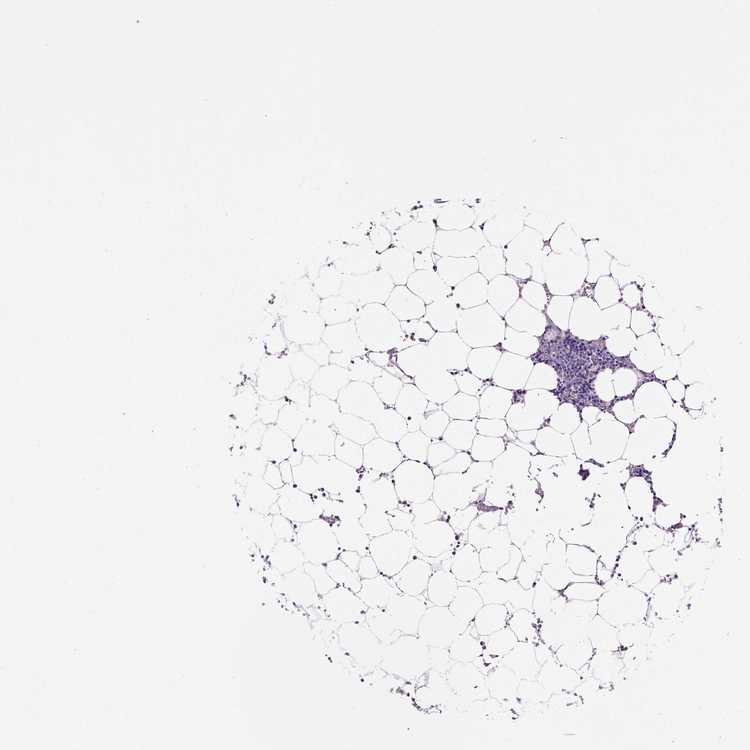

TISSUE PRIMARY DATA BONE MARROW Show tissue menu

BONE MARROW - Antibody stainingi

Antibody staining in the annotated cell types in the current human tissue is reported as not detected, low, medium, or high, based on conventional immunohistochemistry profiling in selected tissues. This score is based on the combination of the staining intensity and fraction of stained cells.

Each image is clickable and will lead to virtual microscopy that enables deeper exploration of all samples and also displays staining intensity scores, fraction scores and subcellular localization as well as patient and tissue information for each sample.

Antibody HPA074314Antibody CAB002500Antibody CAB010893

Hematopoietic cells Not detectedLowMedium